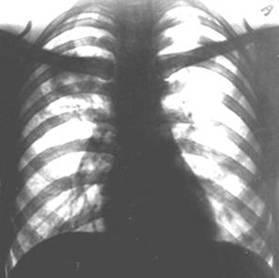

Рис. 9а). Обзорная рентгенограмма грудной клетки ребенка с врожденной воздушной кистой правого легкого в прямой проекции: кольцевидная тень кисты указана стрелками.